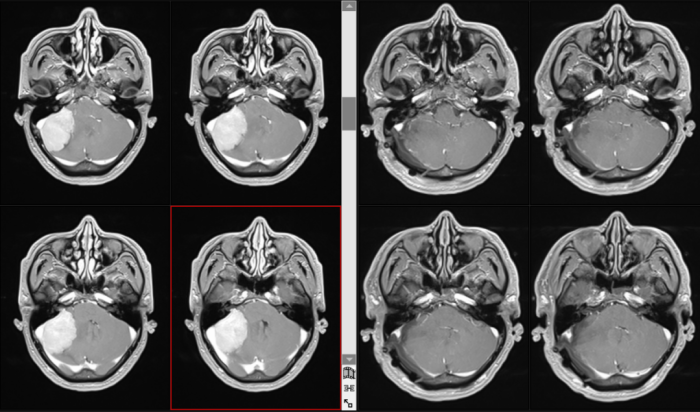

近期,我院神经外科团队成功为一名40岁男性患者实施巨大小脑幕下脑膜瘤近全切除术。该患者肿瘤体积接近5cm,压迫脑干,挤压第四脑室并引发梗阻性脑积水,病情极度凶险。该科团队凭借精湛的显微技术与丰富经验,成功为患者拆除颅内“定时炸弹”,患者术后顺利康复。

患者因反复头痛8月余来到我院神经外科就诊。据患者自述,半年前已在外院检查发现小脑幕下脑膜瘤,但因肿瘤巨大、位置险要、紧邻生命中枢,外院评估手术风险极高,无把握完成手术。

入院后,我院进一步完善影像学检查,初步诊断为右侧小脑幕下脑膜瘤,肿瘤最大径接近5cm,属于巨大脑膜瘤。肿瘤压迫脑干,挤压第四脑室,造成梗阻性脑积水,颅内压力持续升高,患者随时可能发生头痛加剧、意识昏迷、呼吸心跳骤停,病情极其危急。